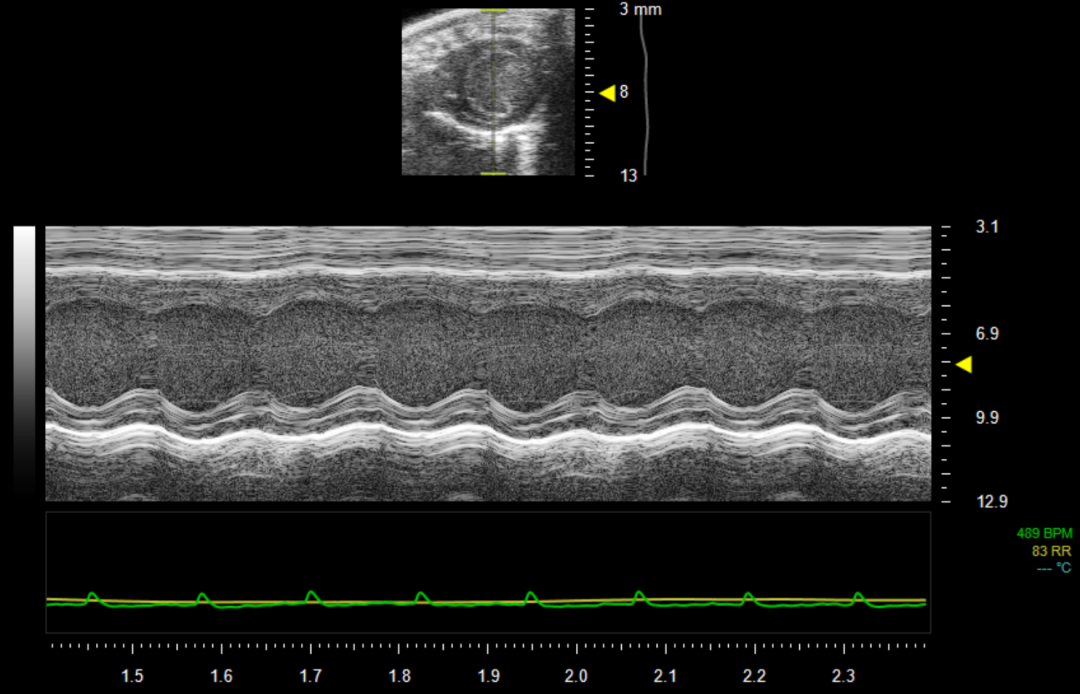

6.获取最佳B-Mode数据后,我们可进一步采集M-Mode数据,将取样线放置在左心室室腔最大面处,如图5所示。

图5 左心室胸骨旁短轴(M-Mode)